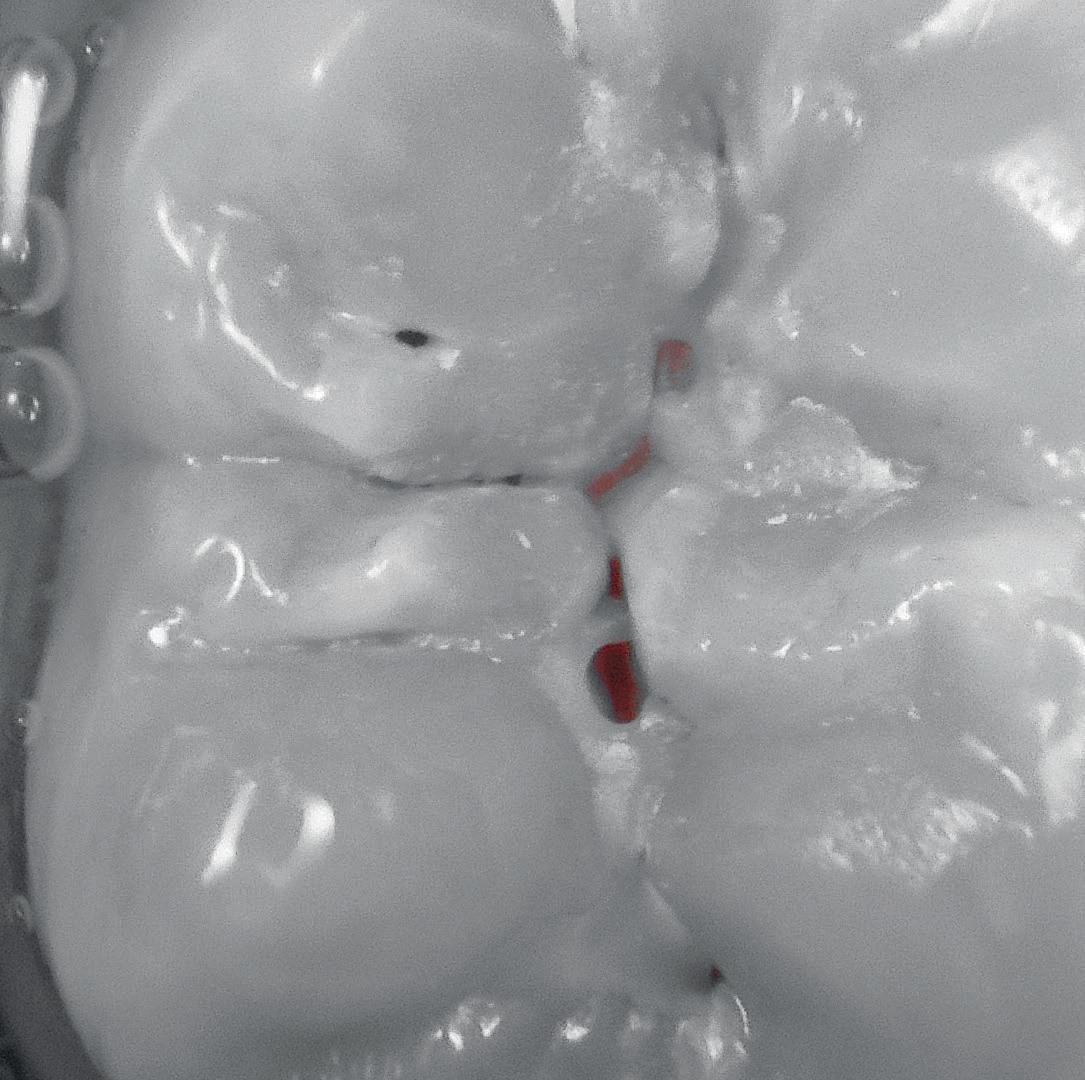

Enhancement of dental plaque and gingival inflammation thanks to chromatic amplification.

DAYLIGHT MODE PERIO MODE

Caries detection by fluorescence technique by LEDs.

ACTEON® DAYLIGHT+ MODE CARIO MODE